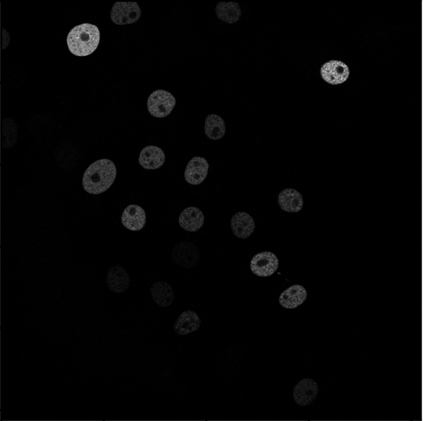

Cell detection in microscopy images is important to study how cells move and interact with their environment. Most recent deep learning-based methods for cell detection use convolutional neural networks (CNNs). However, inspired by the success in other computer vision applications, vision transformers (ViTs) are also used for this purpose. We propose a novel hybrid CNN-ViT model for cell detection in microscopy images to exploit the advantages of both types of deep learning models. We employ an efficient CNN, that was pre-trained on the ImageNet dataset, to extract image features and utilize transfer learning to reduce the amount of required training data. Extracted image features are further processed by a combination of convolutional and transformer layers, so that the convolutional layers can focus on local information and the transformer layers on global information. Our centroid-based cell detection method represents cells as ellipses and is end-to-end trainable. Furthermore, we show that our proposed model can outperform fully convolutional one-stage detectors on four different 2D microscopy datasets. Code is available at: https://github.com/roydenwa/cell-centroid-former